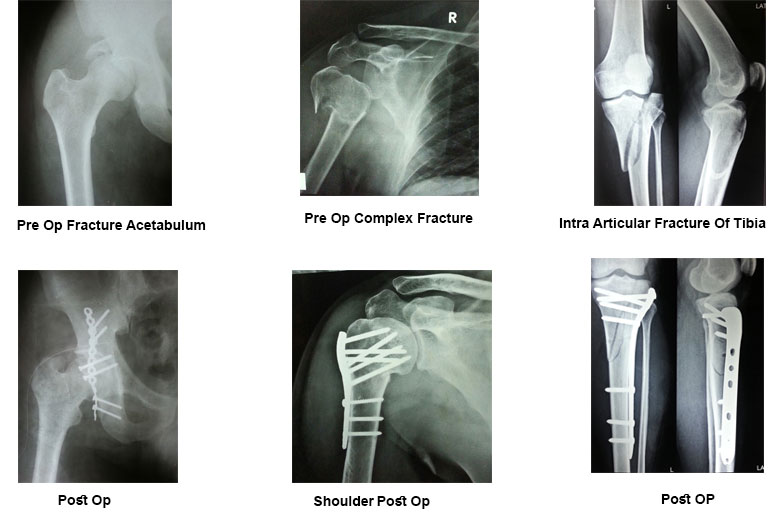

Complex Trauma Surgeries

Fractures and traumatic injuries happen unexpectedly. And while there's no way to prepare for such an injury, it's comforting to know you are in experienced hands. Our experienced surgeons are expert in handling Orthopaedic Trauma situations and perform minimally invasive surgery.

How are complex trauma fractures treated?

The management of fractures has improved considerably with excellent outcomes over the last few decades. These excellent outcomes can be obtained through early intervention by staying relatively active whilst keeping the fractured segment immobilised and subsequent rehabilitation to increase strength and range of motion.

May surgery be required to heal these complex injuries?

Orthopaedic injuries place the patient at risk for various complications, including fat embolism, pneumonia, deep vein thrombosis, and sepsis. Many studies have documented the benefits of early stabilization in reducing morbidity and mortality. Early definitive long bone fixation and external fixation methods have evolved and are considered an integral part of the initial care.

Innovative techniques like computer-assisted surgery continues to develop as technology improves. Uses in trauma include navigation for percutaneous screw placement in trauma surgery and for replacement surgery for reconstruction of complex fractures.

The ultimate target is to enable patients to return to their pre-injury levels. Surgery might be the only option in many of the complex trauma presentations. All these patients should be managed in a collaborative manner. Better understanding and identification of these injuries enables us to optimise the outcomes.